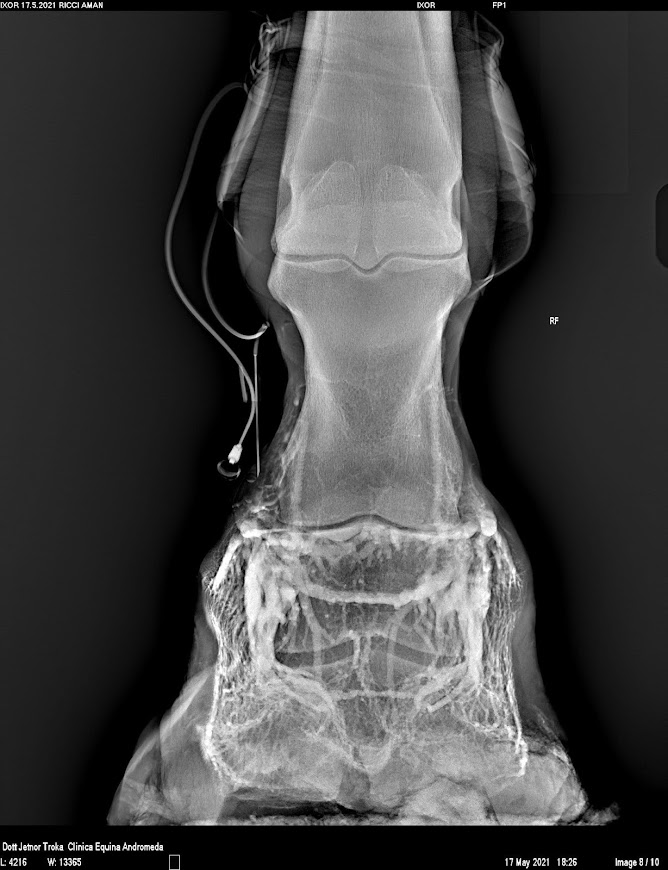

Venografia Digitale

La venografia digitale utilizza il contrasto radiografico per valutare i tessuti molli e la vascolarizzazione del piede, con principale uso in corso di laminite cronica o acuta.

Grazie al materiale di contrasto è possibile evidenziare la vascolarizzazione della zona e l’eventuale danno dell’ingranaggio dermo-ungueale al suo interno. Con questa tecnica infatti è possibile evidenziare la patologia ancora prima che vi sia un riscontro radiografico, permette di determinare la prognosi e un controllo stretto in corso di terapia per valutare la risposta dell’animale.